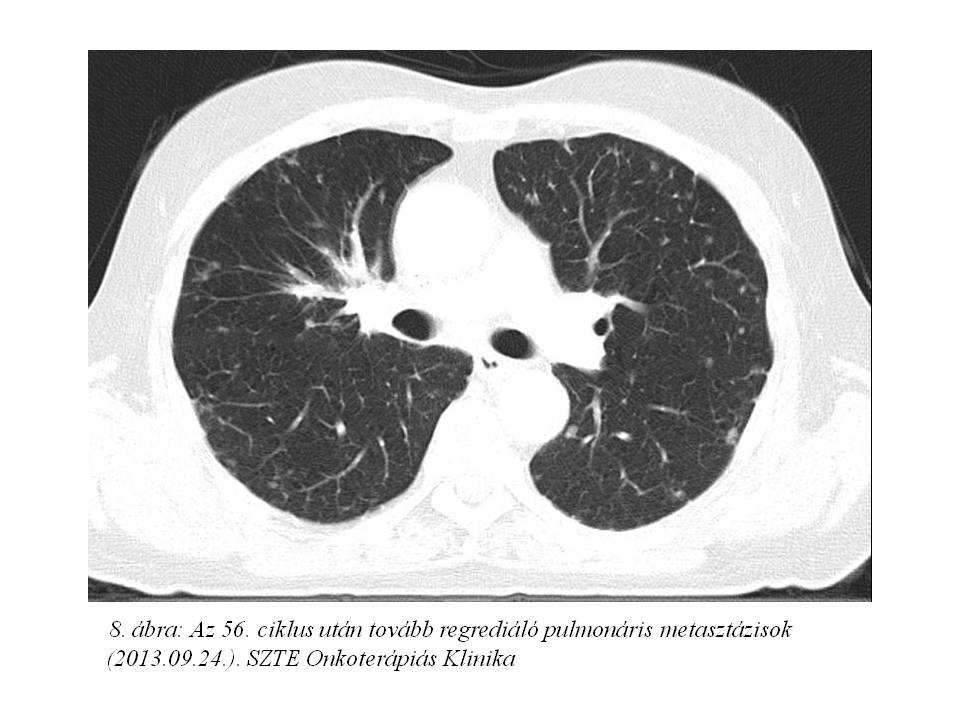

Az 56. ciklus FOLFIRI-bevacizumab immuno-chemotherápiát 2013.09.24-én adtuk, mely utáni CT vizsgálaton (7. ábra, 8. ábra) 80%-os regressziót láttunk az alapvizsgálathoz képest, azonban novum lyticus és scleroticus átépülés jelent meg a jobb csípőlapátban, mely felvetette csontmetasztázis lehetőségét. Ezt egy friss csontscintigráfiás lelet (9. ábra) is megerősítette, és a beteg fokozódó csípő és hátfájdalmai is ezt támasztották alá. Az ossealis propagatio miatt elsővonalas terápiáját felfüggesztettük, fájdalomcsillapítás céljából palliatív irradiatio történt 2013.11.26-tól, a metasztatikusan érintett lumbális IV-V. csigolyákra és medencecsontokra (jobb os ileum, acetabulum), 10x3 Gy frakciódózissal. (10. ábra). Ezen kívül biszfoszfonát (4 mg zoledronsav iv., q4w) kezelés is indult.